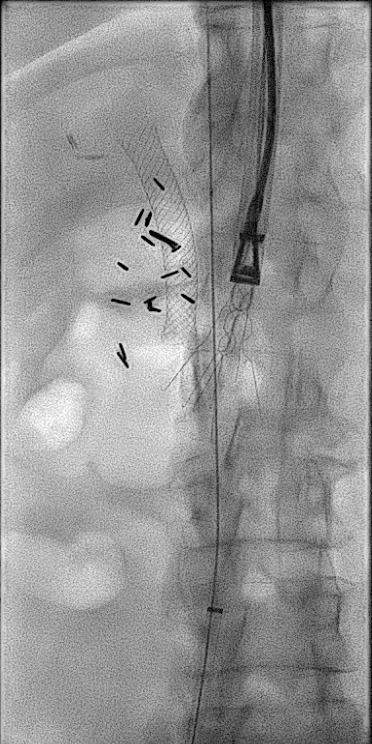

Satisfying to remove a filter that’s older than me! 😀Greenfield with strut perf into duodenum near ampulla, scarring causing biliary obstruction, embedded apex, removed with modified loop snare+ forceps+💪w/ Robert Ford, MD Jefferson Interventional Radiology #filterout Jeffrey F. B. Chick, MD, MPH